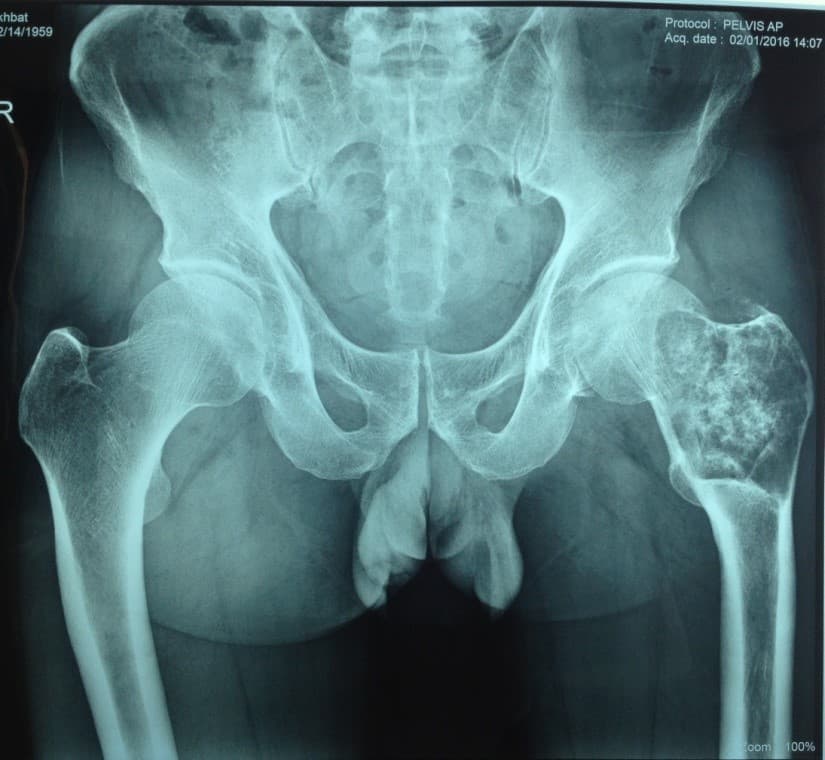

Өвчтөн: С. 57 настай, эрэгтэй

Мэс заслын өмнөх онош: Зүүн дунд чөмөгний түнхний үе орчмын ясны хавдар

Эсийн шинжилгээний хариу: Chondromyxoid fibroma

Шинж тэмдэг: Зүүн түнх, гуя орчим өвддөг, өвдөлт аажим ихсэж байсан, явах зогсох үед өвдөлт нэмэгддэг.

Хөдөлгөөний идэвх: Түнхний үеэр алцайх болон нугалах хөдөлгөөн бага зэрэг хязгаарлагдсан.

Хийгдсэн мэс заслын нэр: Дунд чөмөг-түнхний хавдрын хиймэл үе суулгах мэс засал. Эмнэлэгт хэвтсэн ор хоног 10.

Үе дайрсан ясны анхдагч хавдар, ясны дутмагшлын үед хийгдэх мэс засал image3

Зураг1. Зүүн дунд чөмөгний түнхний үе орчмын ясны хавдар